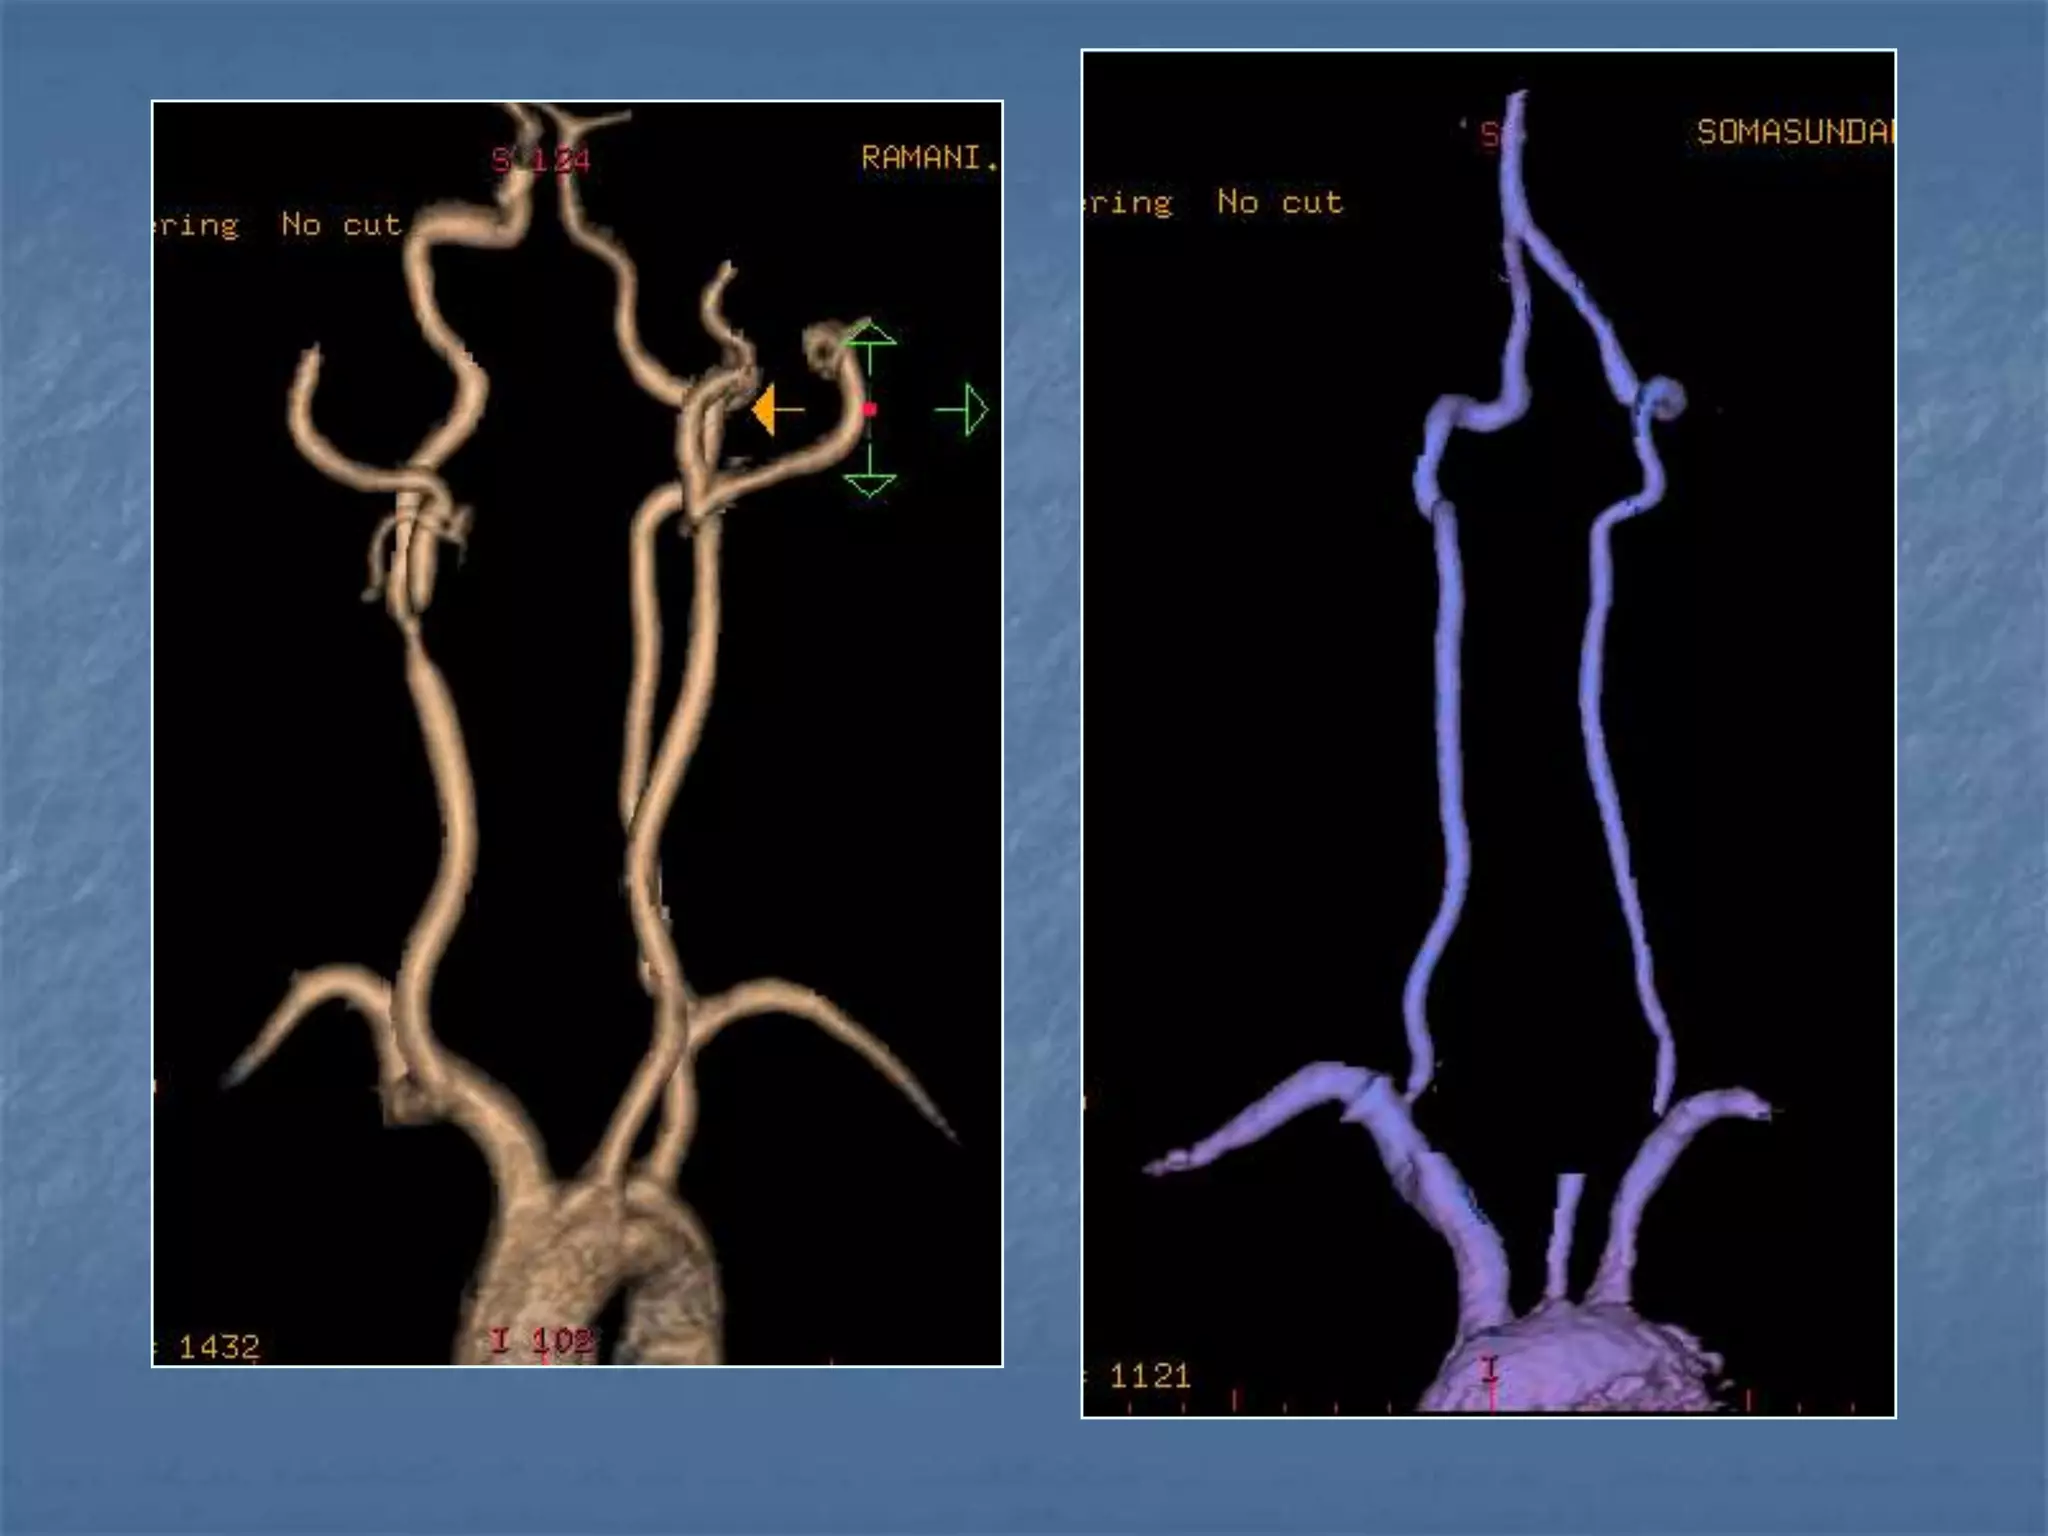

CT Angiography

 Site of occlusion

 Length of occluded

segment

 Arteries beyond occluded

segment – collateral flow

 Detection & exclusion of

large vessel intracranial

occlusion – sens – 98.4%

and spec.-98.1%

JCAT 2001; 25(4):520-8

Subarachnoid hemorrhage

 In the absence of trauma, the most common cause

of subarachnoid hemorrhage is a ruptured cerebral

aneurysm. Cerebral aneurysms tend to occur at

branch points of intracranial vessels and thus are

frequently located around the Circle of Willis.

Common aneurysm locations include the anterior

and posterior communicating arteries, the middle

cerebral artery bifurcation and the tip of the basilar

artery. Subarachnoid hemorrhage typically presents

as the "worst headache of life" for the patient.

Detection of a subarachnoid hemorrhage is crucial

because the rehemorrhage rate of ruptured

aneurysms is high and rehemorrhage is often fatal.